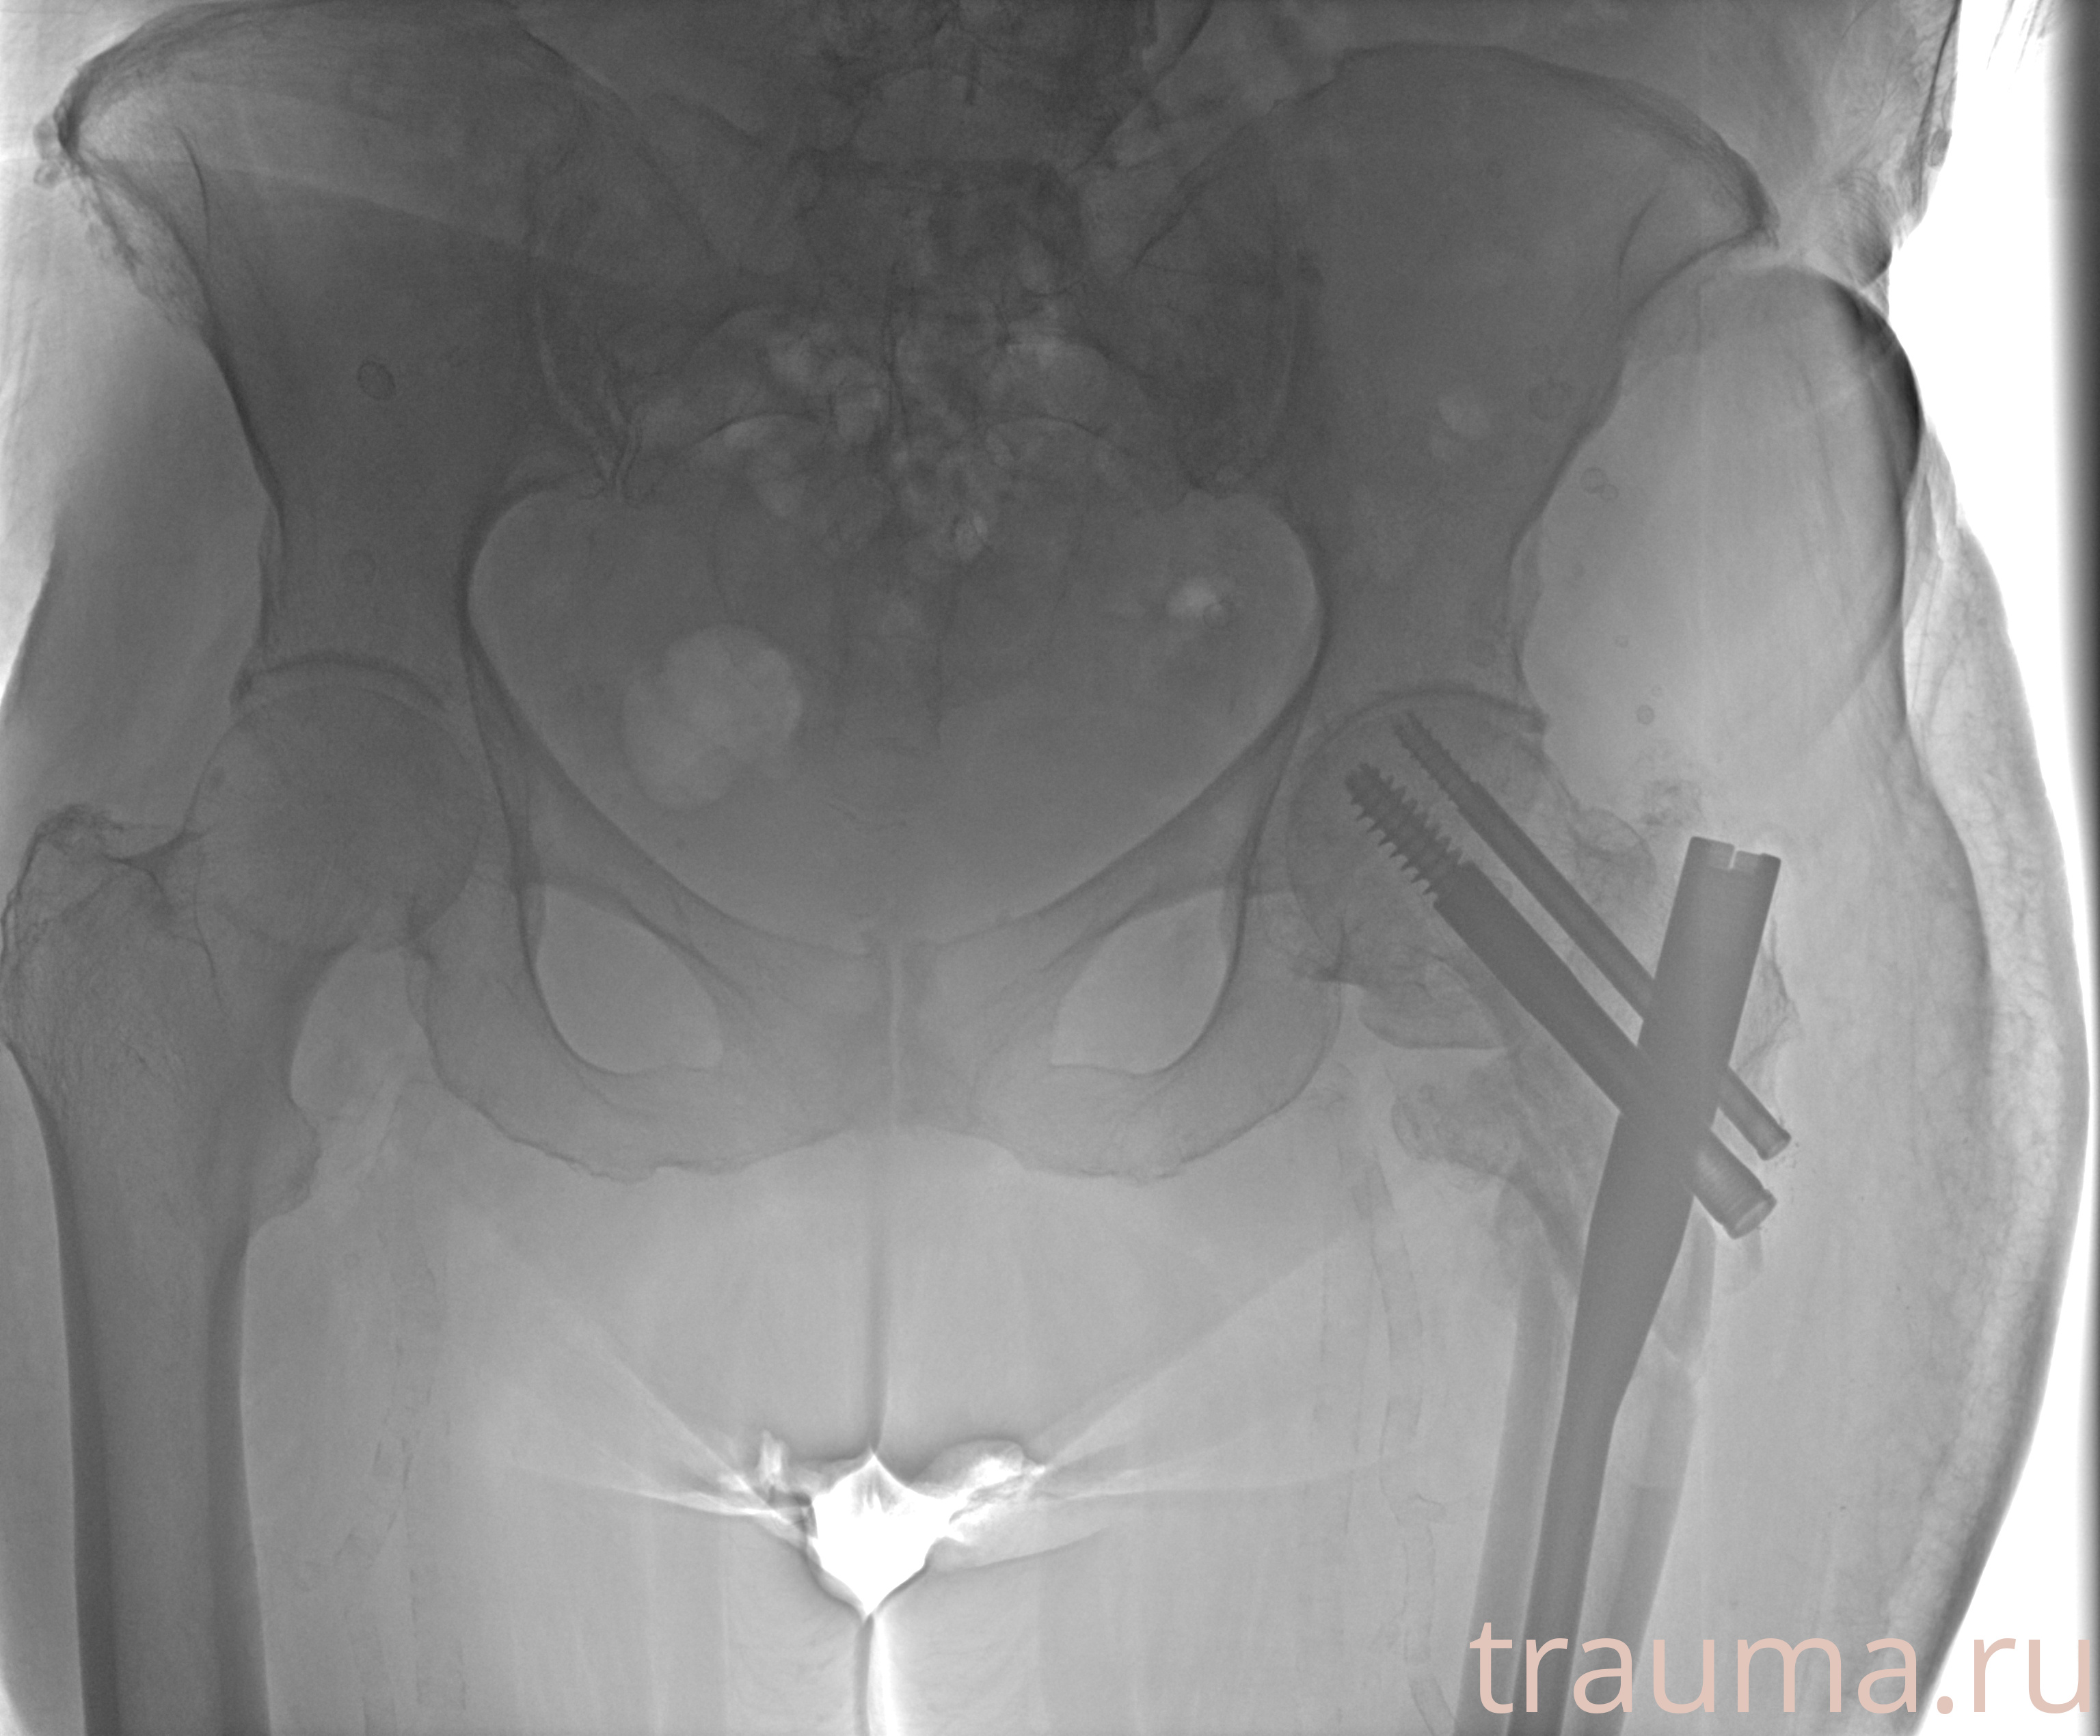

Рентгенограммы

Рентген на дому: по вашему адресу приезжает врач-рентгенолог, травматолог-ортопед с мобильным рентгеновским аппаратом, проводит диагностику травмы или заболевания, делает необходимые рентгенограммы, дает рекомендации по дальнейшему лечению. Получить качественные снимки в домашних условиях возможно благодаря уникальной методике, разработанной МосРентген Центром для института  Склифосовского